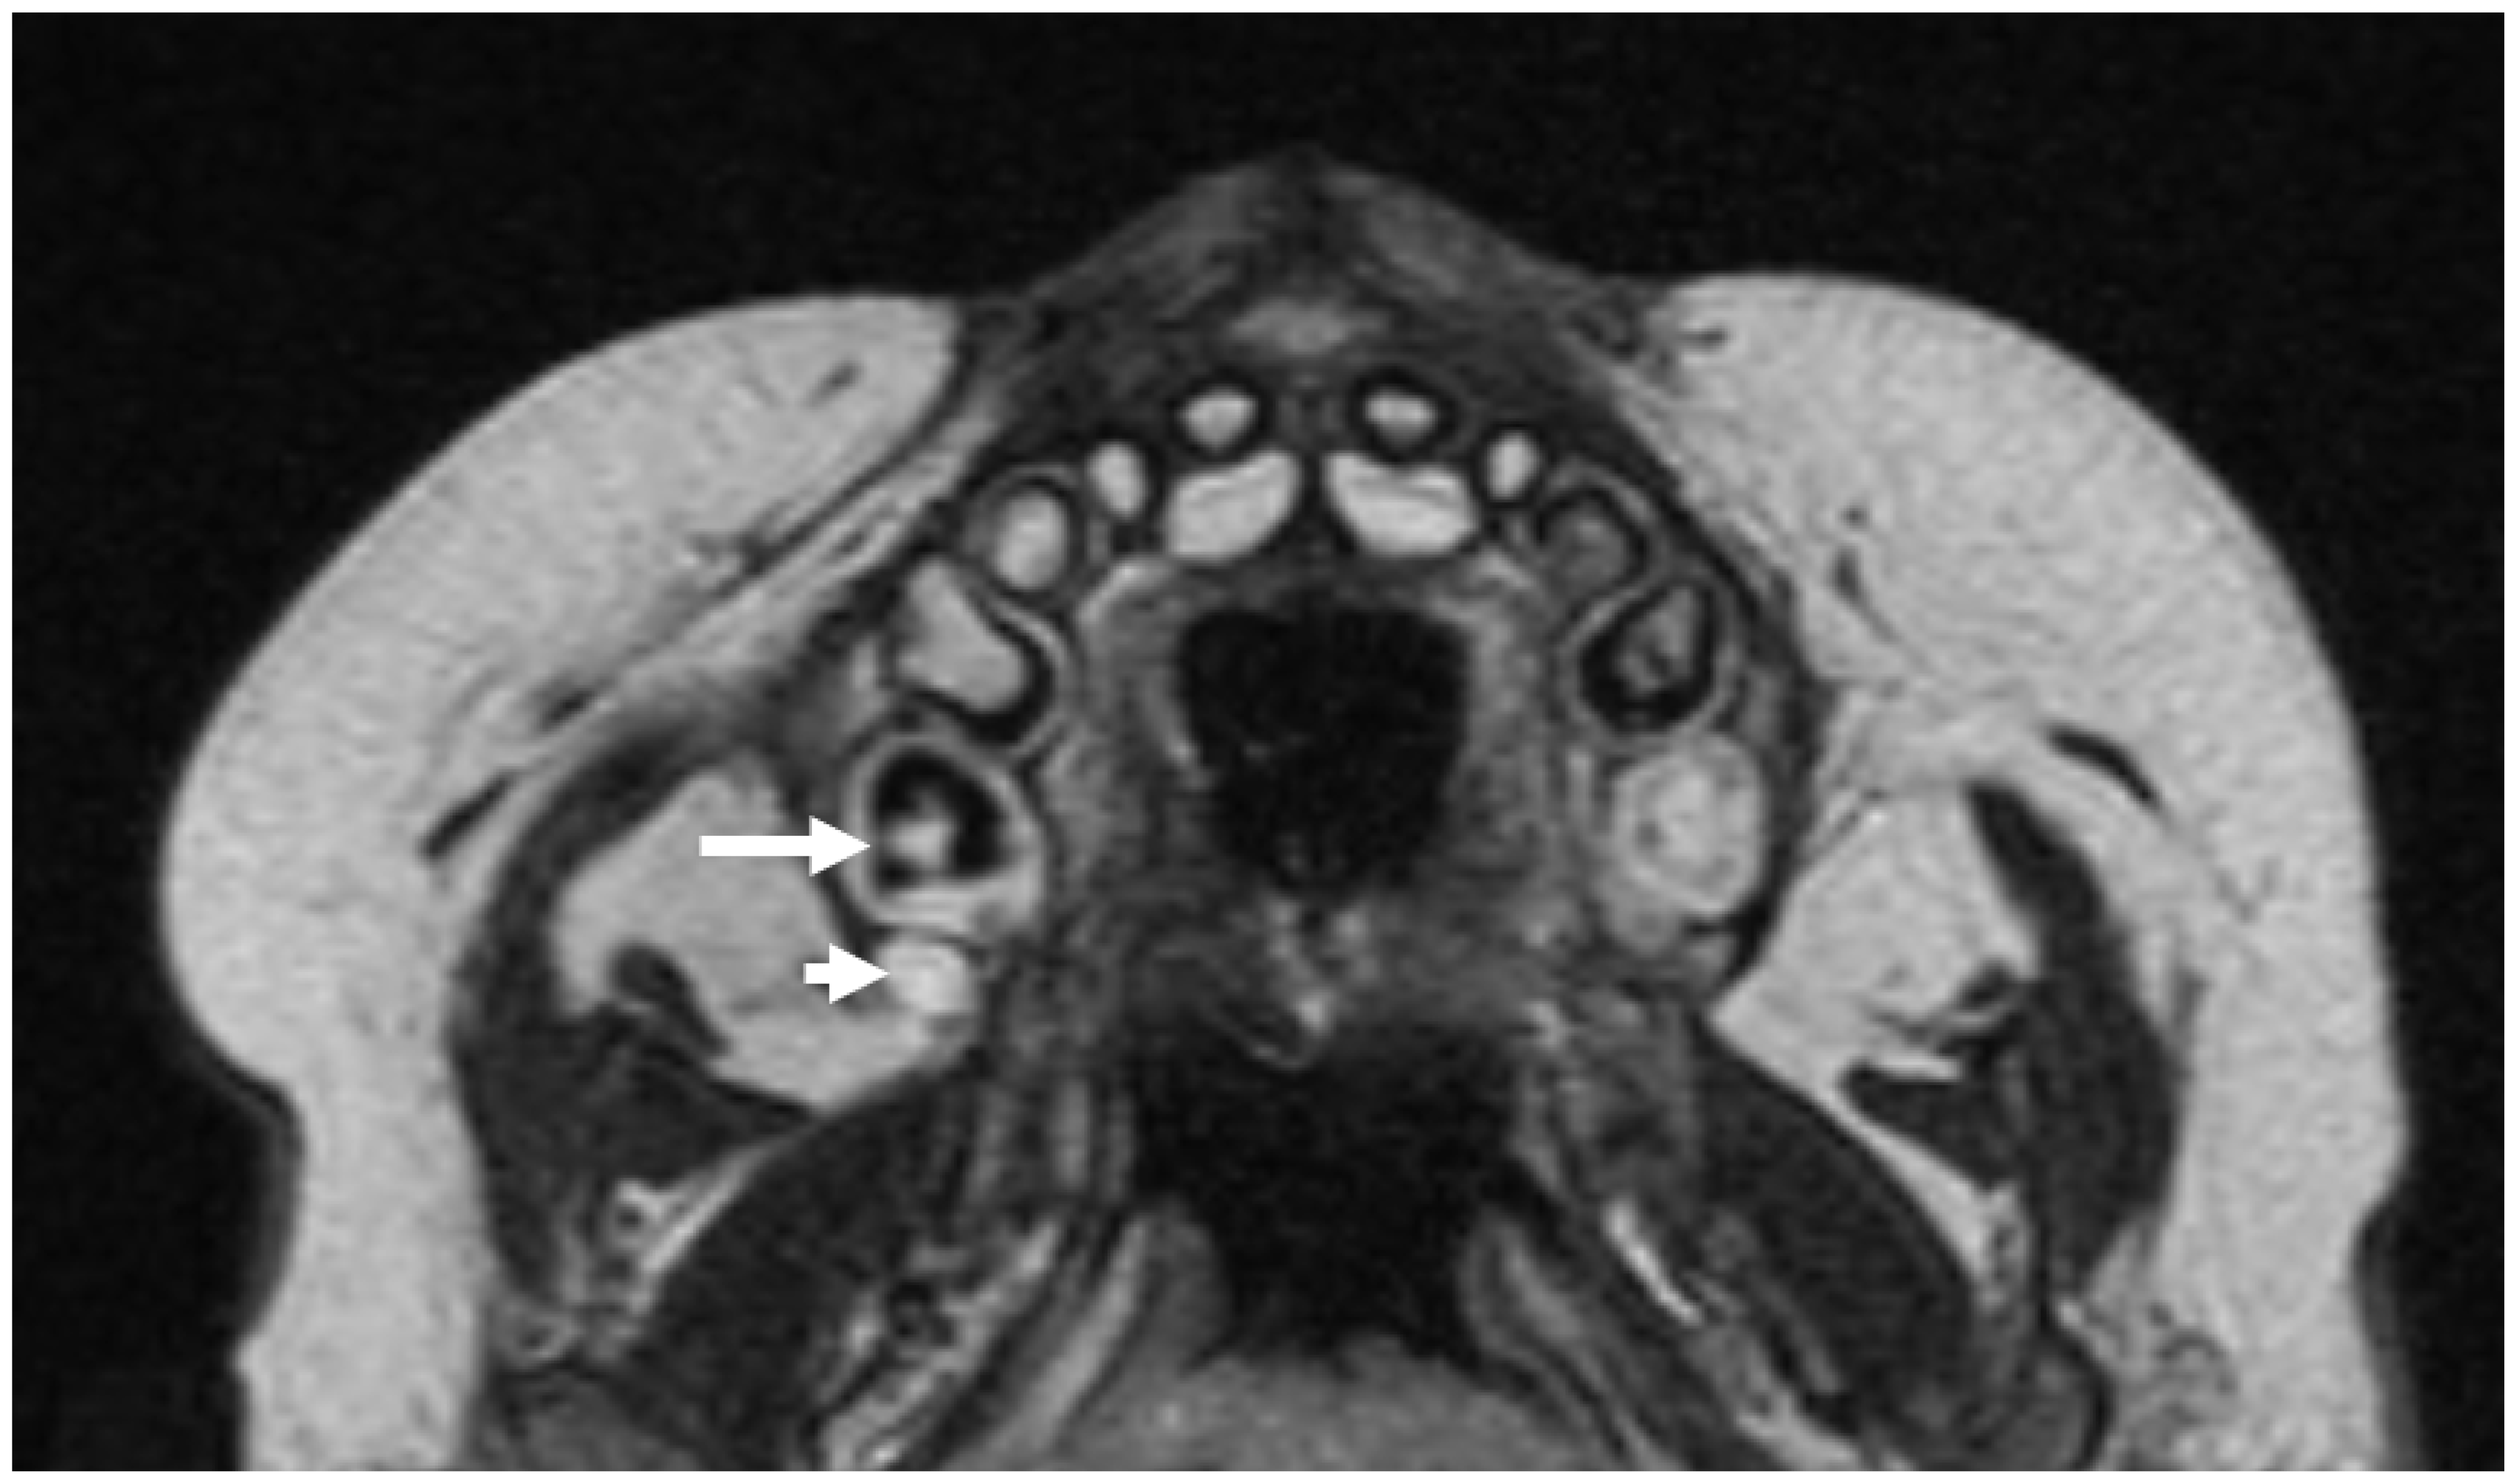

2. Materials and Methods

3. Results

3.3. Radiologic Correlations of Embryological Development

3.4. Application of Principles to Consecutive MR Exams

3.5. Anatomical and Imaging Correlations to Odontogenic Infectious Disease